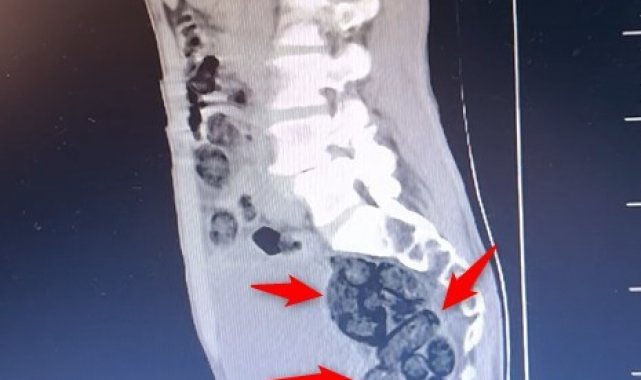

Durumundan şüphelenilen yabancı uyruklu bir yolcu üzerinde arama yapıldı. Yapılan incelemeler sonucunda yabancı uyruklu şahsın midesinde 64 Parça halinde toplam 472 gram uyuşturucu maddesi metamfetamin olduğu belirlendi.

Gözaltına alınan şahsın midesindeki uyuşturucu madde çıkartıldı. Emniyetteki işlemlerinin ardından adliye sevk edilen şahıs, çıkarıldığı mahkemece tutuklanarak cezaevine gönderildi.